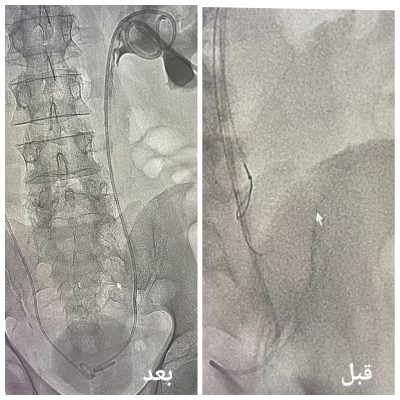

وعلى الفور، قام الفريقان بإعادة فتح حالب المريض بنجاح بإجراء طبي حديث بواسطة منظار الجهاز البولي والأشعة التداخلية في توقيت واحد، حيث تم استخدام الأشعة التداخلية لإزالة الدعامة القديمة بسبب انغلاقها.

وتم تركيب دعامة جديدة أفضل بواسطة الأشعة التداخلية عن طريق فتحة في الجلد لا تتجاوز 1 سم تحت تخدير موضعي.